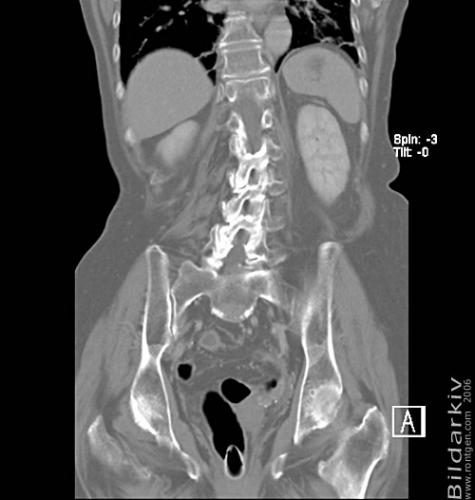

CT colon 37

Datortomografi av tjocktarmen (colon) med infunderad luft i tarmen samt med kontrast i blodbanan. Koronar bildserie.

CT multislice 16